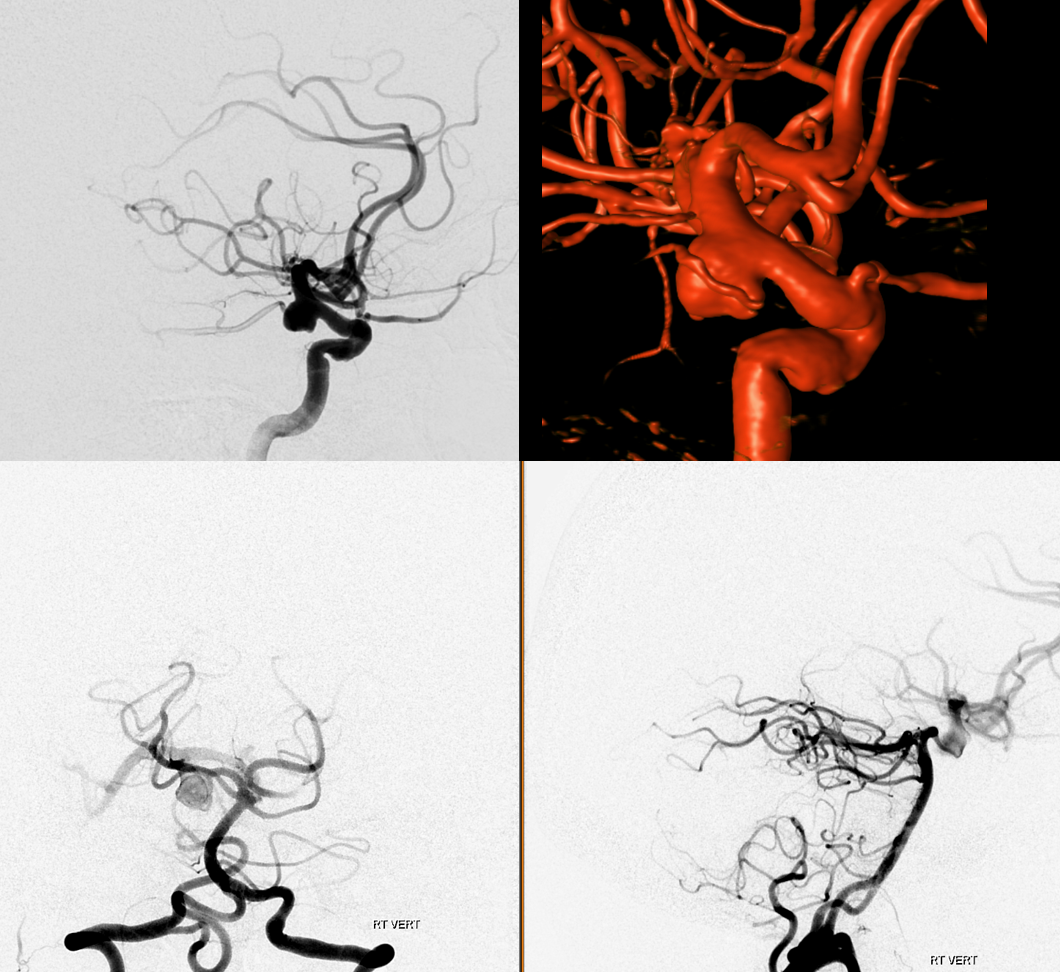

This is a not so aggressive looking PCOM. Not small but also not very ominous-appearing

What to do? Coiling it through P1 risks the thalamoperforator. Undercoiling is not a good idea. The solution is to Pipe across the P1